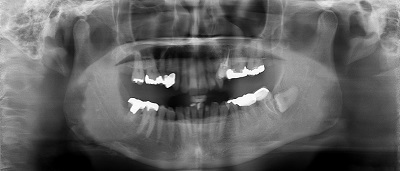

Step-1 CTデータ、X線撮影、模型診査による術前のシュミレーション

Step-5 移植歯の根管治療

(移植歯は残念ながら神経が死んでしまうため、移植後3週間目くらいに根管治療を行います)Step-6 移植歯の補綴処置

(移植した歯が適正なかみ合わせで機能するよう仮歯をいれしばらく機能を確認したのちに最終的な被せ物を入れていきます)※移植部位の状態や移植歯の状態により適応出来ない場合もあります。

右上の親知らずを左下6番目に移植